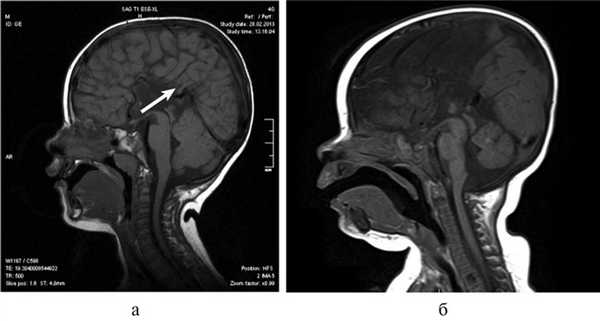

Рис. 1. КТ и МРТ головного мозга (сагиттальная, фронтальная проекции) и внешний вид больной Т., 8 мес. а — КТ: АМТ (стрелка); б — микрофтальм слева на МРТ (стрелка); в — внешний вид пациентки с множественными стигмами дизэмбриогенеза.

Рис. 2. Результаты обследования больной С., 8 лет. а, б, в — МРТ головного мозга (сагиттальная и аксиальная проекции): сочетание АМТ и диффузной пахигирии (стрелки).

Рис. 3. МРТ головного мозга (сагиттальная проекция) больной С., 7 лет. АМТ (стрелка).

Важной находкой при АМТ на МРТ является параллельная ориентация тел боковых желудочков по отношению друг к другу (рис. 4, а), расширенные фронтальные отделы желудочков, так называемый «симптом ухвата».

Рис. 4. МРТ головного мозга больной К., 4 года. АМТ. Аксиальная проекция: а — аномальная параллельная ориентация тел боковых желудочков по отношению друг к другу (стрелка); б — фронтальное сечение: деформация передних и задних рогов боковых желудочков, своеобразный U-образный характер фронтальных отделов боковых желудочков (стрелка).

При МРТ мы обращали внимание также на описанное в литературе [12] изолированное расширение задних рогов — кольпоцефалию, обусловленную гипоплазией ассоциативных трактов белого вещества затылочных долей. Диагностический ряд на МРТ дополняют отсутствие нормально сформированных перикаллезных извилин (рис. 5, а) и радиальная центростремительная позиция борозд медиальной поверхности теменной доли (рис. 5, б).

Рис. 5. МРТ головного мозга больного А., 3 года. АМТ. а — сагиттальная проекция. Отсутствие нормально сформированных перикаллезных извилин (стрелка), б — высокое положение III желудочка, радиальная центростремительная направленность борозд медиальной поверхности теменных долей.